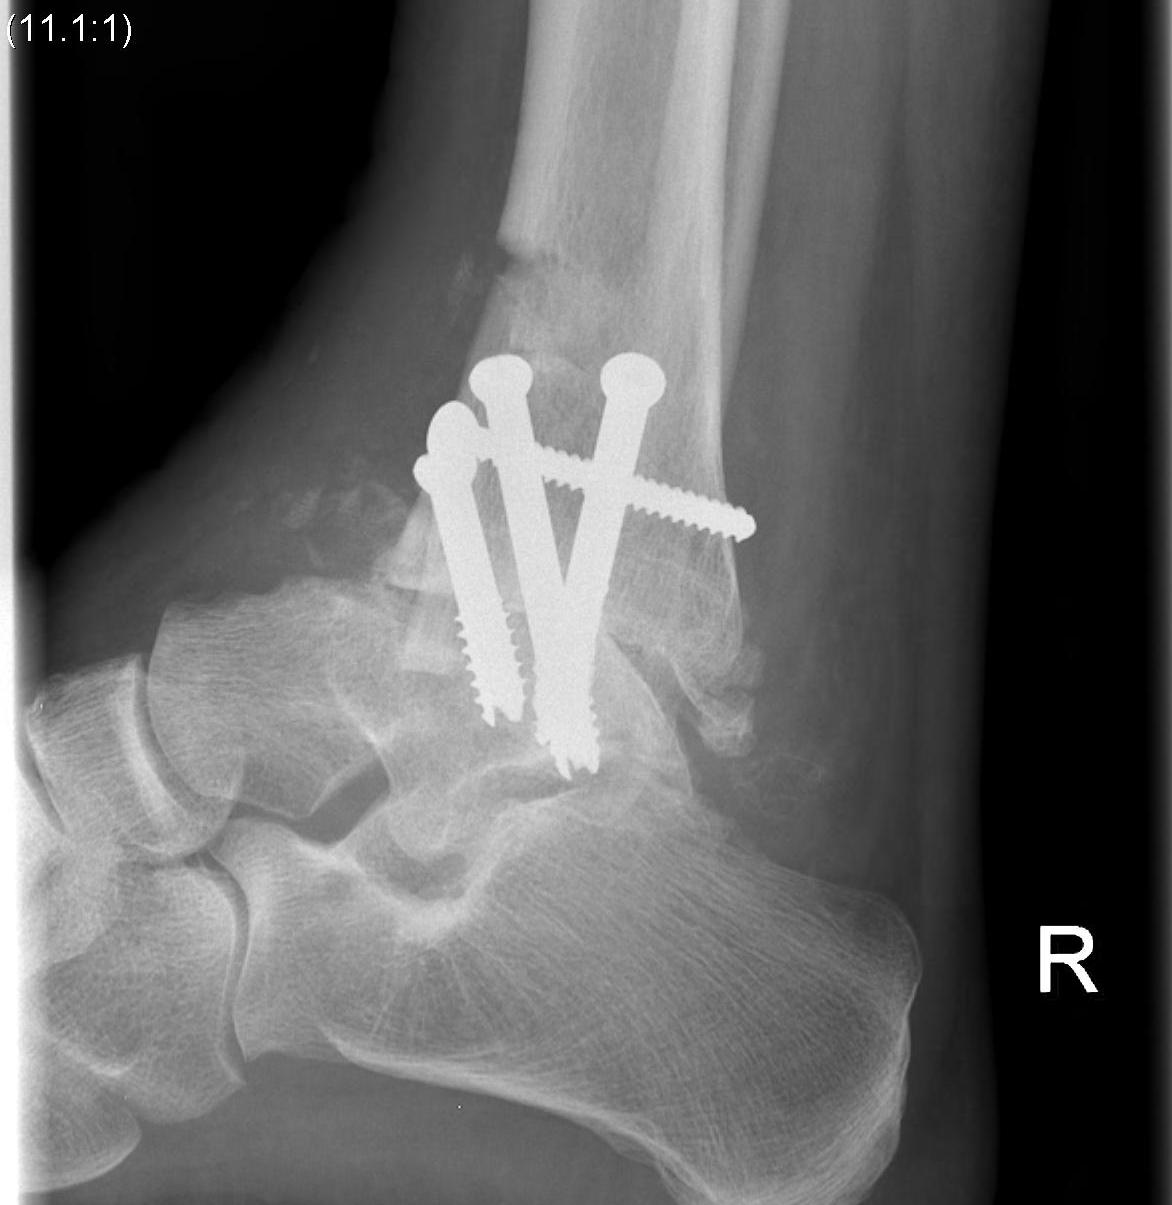

Pantalar fusion with hindfoot nail

talus avntalus AVNPantalar fusion

Arthrodesis

- Blair fusion - sliding tibial bone graft and tibio-talar fusion

- tibio-talar-calcaneal (pantalar) fusion with hindfoot nail